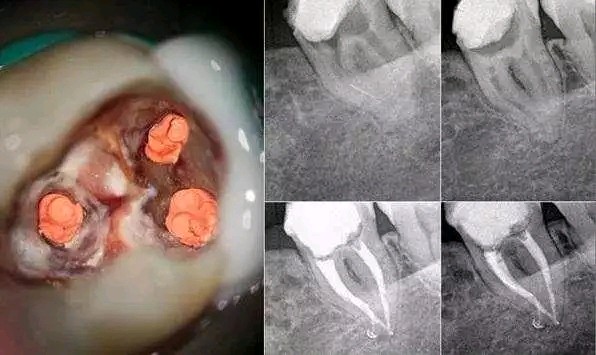

牙片是治疗过程中重要的手段之一,其作用是:

在治疗前用于发现病变程度、范围;

治疗中引导治疗、确定治疗范围和治疗深度;

治疗后观察疗效。